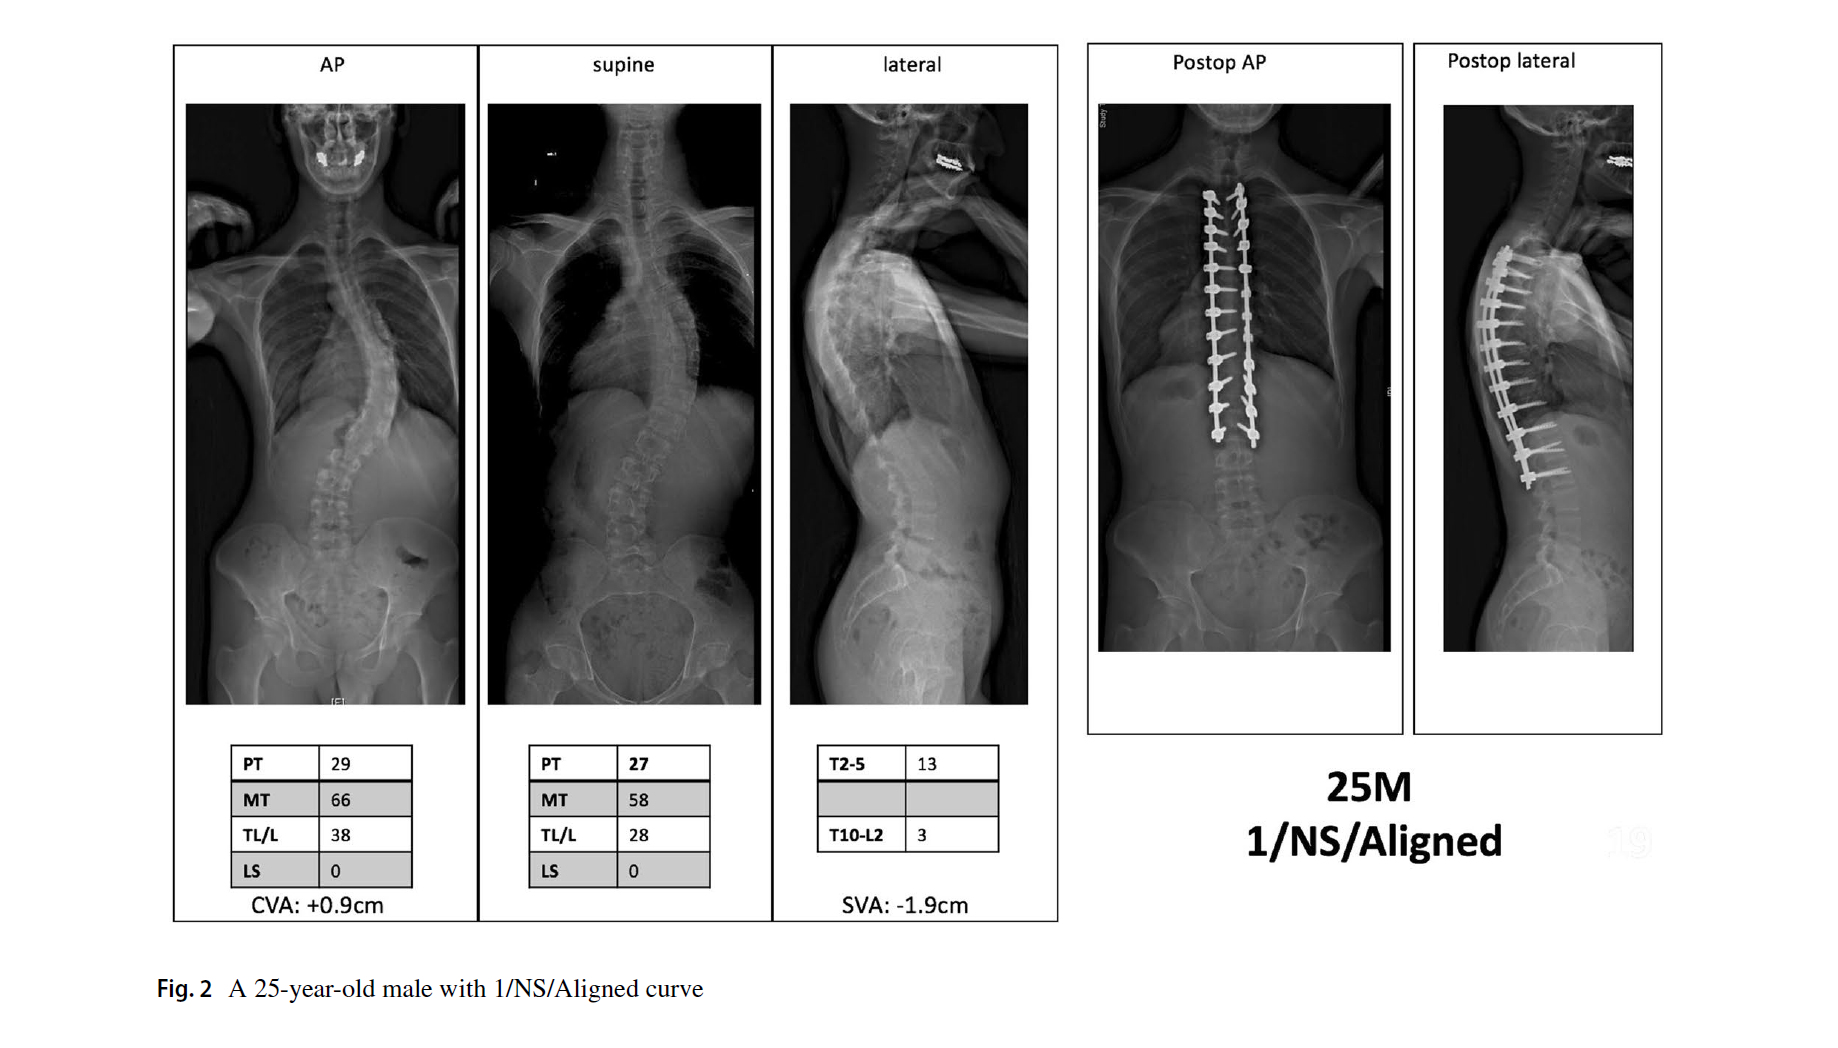

1. 曲线类型分为6型,与Lenke AIS完全一样。但结构弯的标准为:仰卧位全长位Cobb角大于35度,或者后凸大于20度。这与AIS不同,也摒弃了bending位片。

2. 腰骶椎修正,是本分型的特别和关键之处。定义为仰卧位片L4上终板到S1上终板的Cobb角。大于20度为结构弯(S),需要融合腰骶段。小于20度为非结构弯(NS),不需要融合腰骶段。

3. 脊柱平衡修正包括了冠状位、矢状位和冠矢合并的平衡状态。标准与SRS基本一致,冠状位失衡CVA≥40mm,矢状位失衡SVA≥40mm。排列组合,共有Aligned、Sag Malalign、Cor Malalign、or Comb Malalign 4种类型。如果脊柱失衡,需要按SRS标准矫正。

文中的病例片子很漂亮,看图知意,很容易让读者理解这个分型。